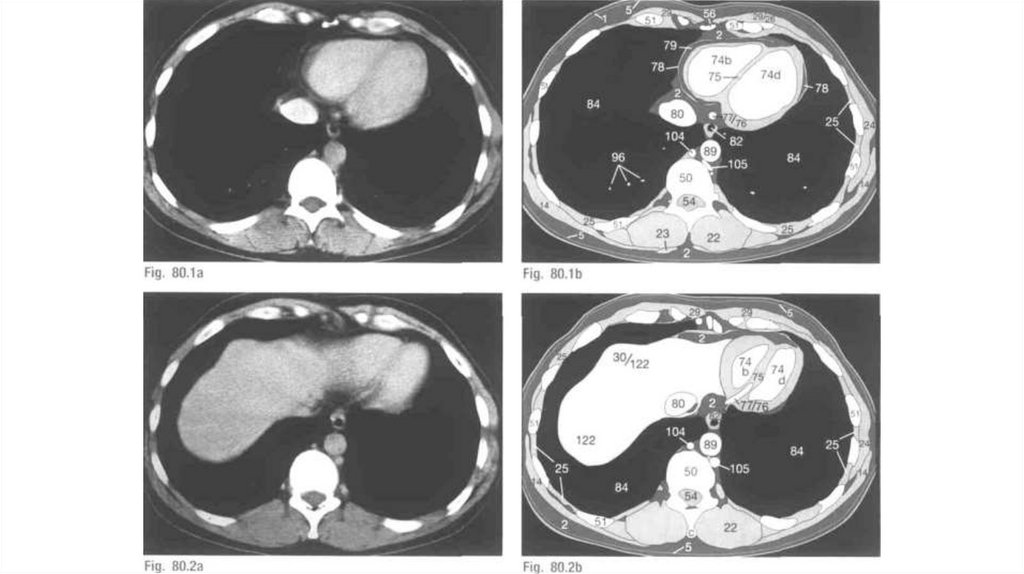

Томографические методы

1.

2.